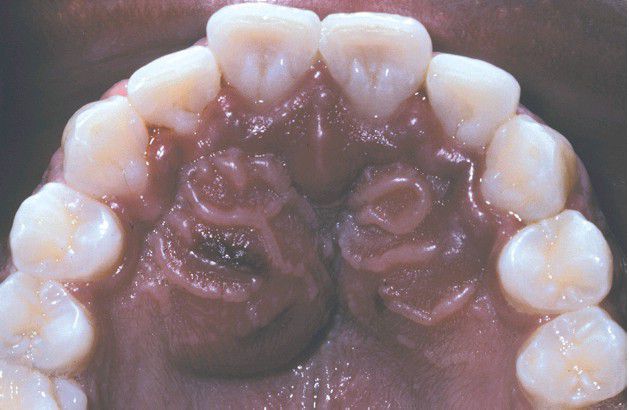

Periapical Abscess

. Bilateral soft tissue swelling of the anterior palate.